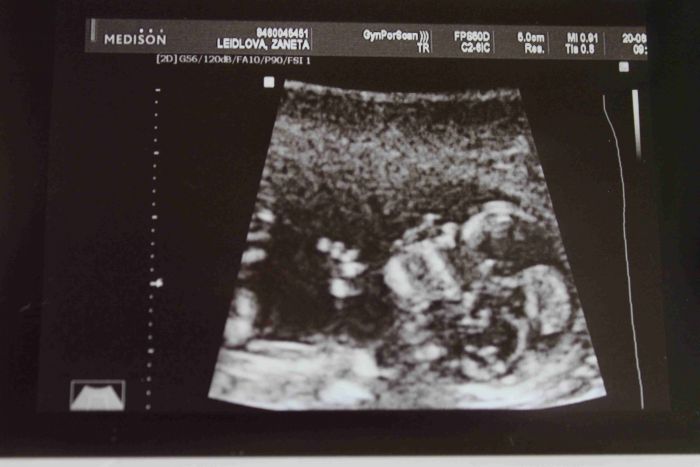

Ahoj holky, tak už máme za sebou sreening, prcek je 7,2 cm velký, je to čiloušek, pořád sebou mrskal, dr.už byla celá nervózní z toho, že ho nemohla pořádně změřit a předběžně řekla, že to vypadá na holčičku a ikdyž si ji i tajně přejeme díky samých chlapákům v rodině, stejně mám pocit, že čekáme klučíka, no uvidíme